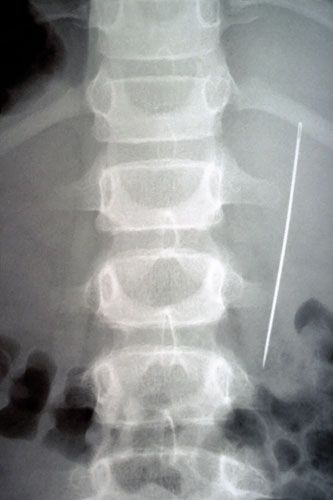

South ­Africa A needle rammed into the victim’s back. Photograph: Courtesy Hermann Vogel